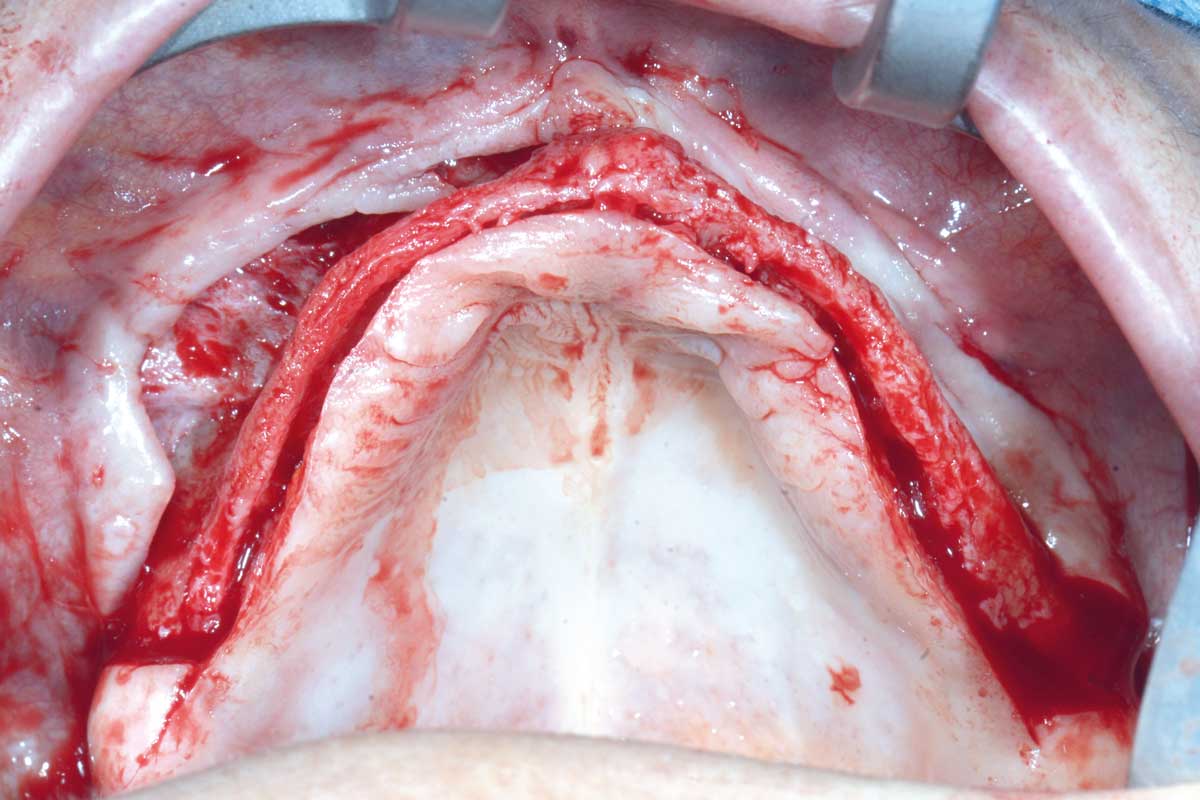

Full arch GBR using cerabone®, maxgraft® and Jason® membrane with simultaneous implantation of 6 Straumann® implants - Dres. A. Signorio and G. Molina